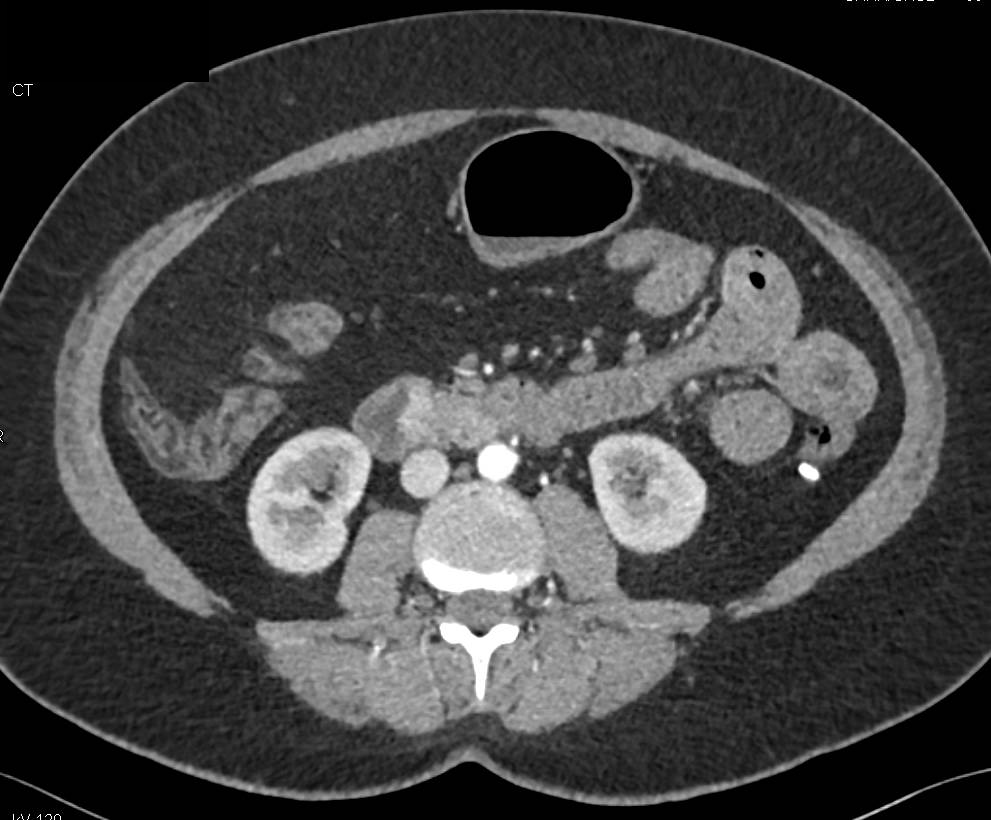

Carcinoid Tumor of Ampulla with Enhancing Peripancreatic Nodes